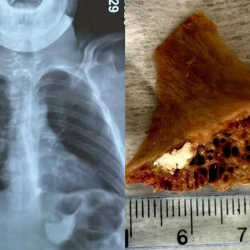

Бишкекте 15 жаштагы өспүрүм сөөк жутуп алып, кызыл өңгөчүнө тыгылып калган. Бул тууралуу Бишкек шаардык медициналык тез жардам балдар клиникалык ооруканасынан билдиришти.

Маалыматка ылайык, бала 4 сантиметр өлчөмдөгү сөөктү жутуп алган. Шаардагы эки ооруканада сөөктү чыгара алышпагандыктан, бала Бишкек шаардык медициналык тез жардам балдар клиникалык ооруканасына жеткирилген.

"Дарыгерлер ыкчам түрдө операция жасап, тыгылып калган сөөктү ийгиликтүү алып чыгышты. Оор абалда келген балага дароо керектүү медициналык жардам көрсөтүлүп, операцияга жасалды", - деп белгилешти ооруканадан.